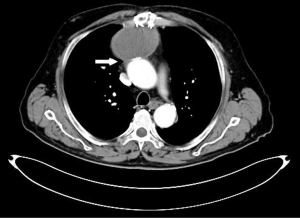

In 115 patients evaluated using Duke’s criteria for IE, TEE had a sensitivity of detecting abscesses of 48%, whereas 64% missed detecting abscesses that were located near bulky calcific deposits on the posterior mitral valve leaflet (5). MDCT has increased spatial resolution and unaffected by acoustic shadowing. MDCT can evaluate coronary artery anatomy (in the setting of ischemic disease or congenital defects). The enhanced spatial resolution permits the evaluation of perivalvular lesions (abscesses, fistulas, pseudoaneurysms, and extension into the cardiac skeleton) (Figure 4). MDCT can also detect primary or IE related pneumonic diseases as abscesses or necrotic deposits. It facilitates effective imaging of the tricuspid annulus and leaflets (Table 4) (7).